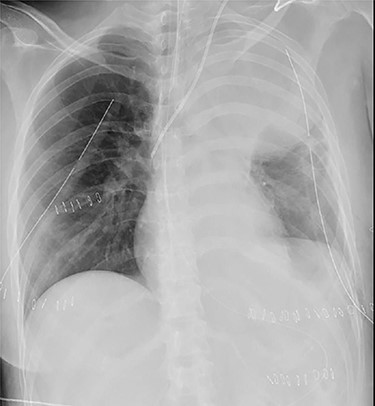

A 38-year-old woman with schizophrenia committed suicide by a self-infliction of sharp force into the chest and abdomen. She presented to our hospital in a critical condition. On arrival in the emergency room (ER), she developed hemorrhagic shock, which leads to an emergent abdominal damage control surgery under general anesthesia. She lost cardiac activity in the operating room during exploratory laparotomy. A left-sided basal thoracostomy, cross-clamping of the descending thoracic aorta, and open cardiac massage were also performed. She received gauze packing at the bleeding point and temporarily close the abdomen and chest wall. After the surgery, she was transferred to the intensive care unit with mechanical ventilation and recovered from hemorrhagic shock. Two days later, a second-look laparotomy was performed. ER doctors verified the hemostasis and closed the patient’s abdomen and chest. On the same day, a chest radiograph revealed pulmonary atelectasis of the left upper lobe (Fig. 1). Computed tomography (CT) revealed alveolar bleeding, pneumonia and atelectasis of the left upper lobe (Fig. 2). Despite antibiotic therapy and repeated endobronchial sputum aspiration, radiologic findings were not improved. On the seventh postoperative day, she was referred to our department for suspected lung abscess. When compared to the chest CT images on the day of initial surgery, pulmonary torsion was suggested (Fig. 3A). The sagittal CT images were reconstructed, and the torsion of the left upper lung lobe was diagnosed (Fig. 3B). Therefore, an emergency left upper lobectomy was performed through a left thoracotomy. Intraoperatively, the left upper lung lobe was rotated clockwise and was hemorrhagically and congestive infarcted. Due to severe pulmonary congestion, it was difficult to obtain the surgical field of view. The pericardial sac was opened and the intrapericardial isolation of the left upper pulmonary vein was performed. To prevent separation of the thrombus and necrotic material in the left upper lobe, we first dissected the left upper pulmonary vein before resolving the torsion and performing the lobectomy. She had a complete pulmonary fissure. Moreover, only one first pulmonary artery branch had ruled the approximately pulmonary arterial flow of her left upper lobe. The left upper lobectomy was performed. The patient made an uneventful recovery.

Chest roentgenogram of 2 days after initial emergency operation.